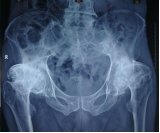

2、髋、膝关节置换手术经验丰富,完善的快速康复方案,手术更微创,无需输血,有效纠正畸形、消除疼痛,可迅速下地,恢复正常活动功能。

髋关节置换